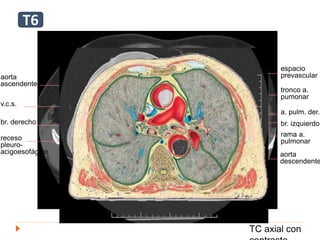

aorta

ascendente

v.c.s.

br. derecho

receso

pleuro-

acigoesofágico

rama a.

pulmonar

tronco a.

pumonar

a. pulm. der.

br. izquierdo

descendente

espacio

prevascular

TC axial con

E

T6